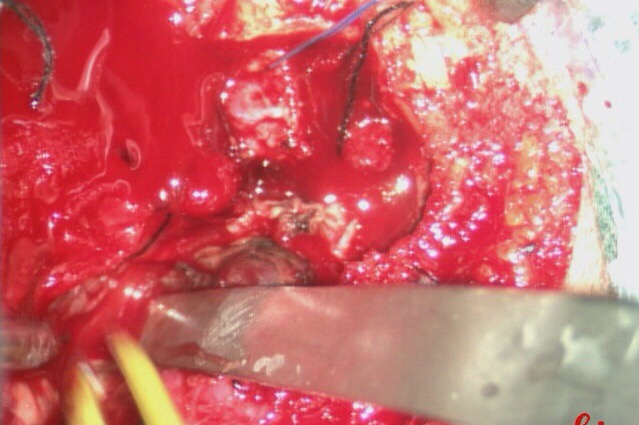

介入手术完成后,行开颅手术治疗。可直接切断经颈外动脉对瘤体的供血。

沿着肿瘤边缘分离肿瘤。

术中出血约1500ml.